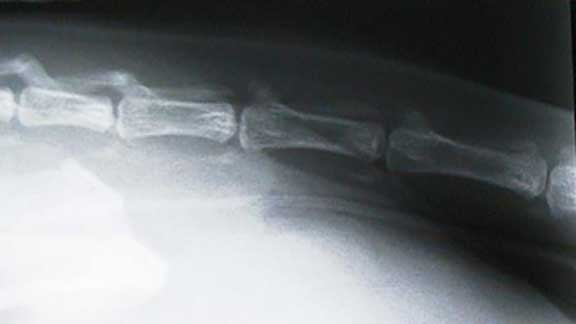

Xray of Normal Elbows in a Dog

These two elbows are normal

Xray of an Arthritic Elbow

This elbow from a different pet shows advanced arthritis, as evidenced by the moth-eaten appearance. It is probably secondary to elbow dysplasia